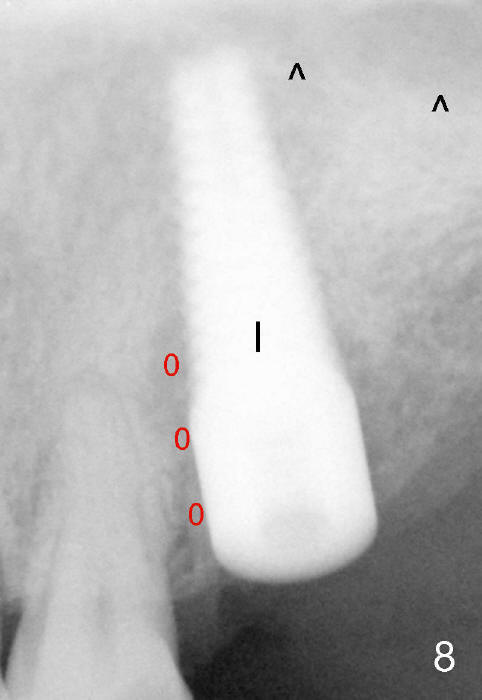

Fig.5 is an illustration showing the socket after extraction. The osteotomy is intentionally placed distally (Fig.6 arrow: pilot drill). In case the patient agrees to have ortho treatment, there will be space to correct the upper midline (7). If not, a molar crown will be fabricated. By the time a 4.5x20 mm tap is inserted (Fig.7 T), the mesial gap is visible (*). When a 6x20 mm implant is placed (Fig.8 I), bone graft is placed buccally (Fig.2, as planned) and mesially (Fig.8 red circles, as compared to Fig.1). The implant has to be as large and long as 6x20 mm to get primary stability (insertion torque 50/60 Ncm). The apex of the implant is close to the sinus floor (Fig.8 ^) or in fact the nasal floor (Fig.9 N). There appears bone growth in the mesial gap 3 months postop (Fig.10 *). There is no bone loss 2.5 years post cementation (Fig.11).